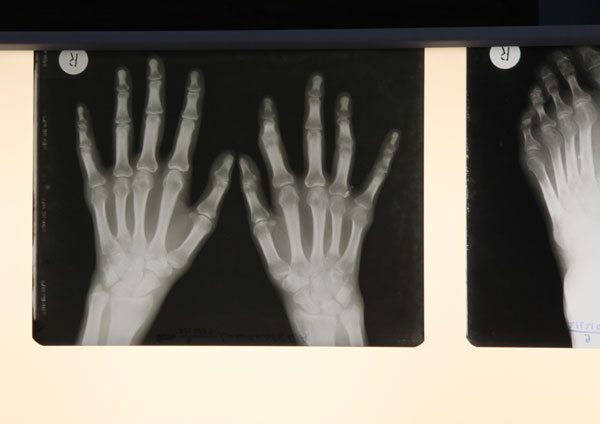

В отделении ревматологии пациентам оказывается специализированная, в том числе высокотехнологичная медицинская помощь при следующих заболеваниях:

• ревматоидный артрит (в том числе серонегативный)

Отделение на базе многопрофильного стационара позволяет обследовать пациентов с привлечением высококвалифицированных консультантов, современных лабораторных и инструментальных методов исследования: компьютерная томография, МРТ, ПЭТ, рентгеновская денситометрия, широкий спектр иммунологических исследований, молекулярно-генетичеcкое исследование и др. На отделении разработаны и широко внедрены методики диагностики ревматологических заболеваний на ранних этапах развития: капилляроскопия, малоинвазивная биопсия малой слюнной железы, нефробиопсия, биопсия печени и кожно-мышечного лоскута. Специалисты отделения имеют большой опыт использования биологических препаратов. Возможности терапии включают в себя: современные программы интенсификации, в том числе в вариантах сочетаний пульс-терапии ГКС и высокими дозами цитостатиков (метотрексат, циклофосфан), режимы полихимиотерапии, синхронной интенсивной терапии.